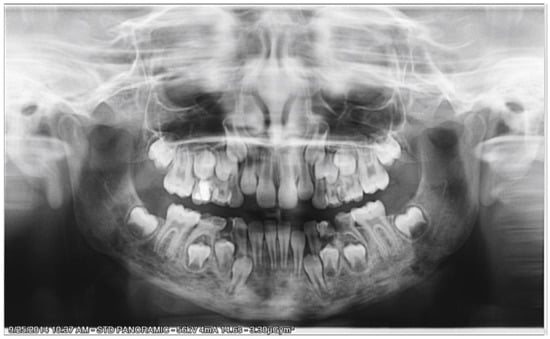

2.1. Initial Diagnosis and Initial Surgical Management

2.2.1. Initial Examination